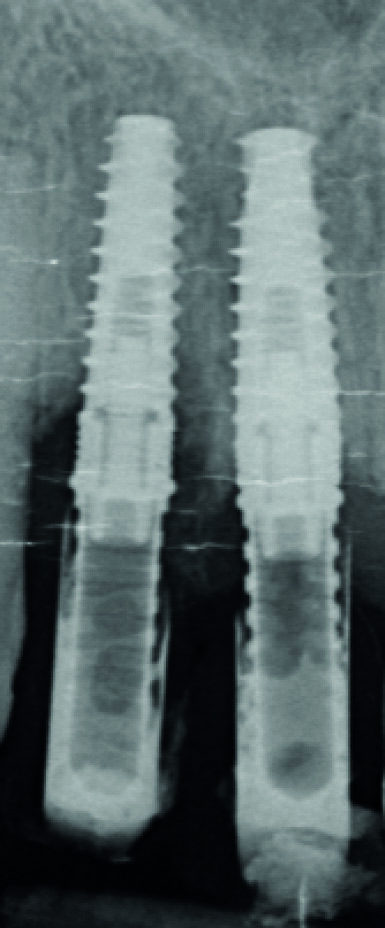

Me M. Ler, âgée de 71 ans lors de la chirurgie, ne présente pas d’antécédents médicaux particuliers, à l’exception d’un cholestérol stabilisé avec des statines (Tahor 10). Elle est traitée depuis 2007 pour une parodontite sévère qui est aussi globalement stabilisée cliniquement, radiologiquement et bactériologiquement. Nous avions déjà réalisé un traitement implantaire en 21 (2008) et 23 (2013) (Fig. 2). La patiente souhaite maintenant mettre des implants en 11 et 12 car les mobilités modérées de ces dents commencent à la gêner dans sa vie quotidienne.

Fig. 2 : Bilan radiologique « long-cône ». Notez la sévérité des pertes d’attache, mais qui sont bien stabilisées depuis 12 ans.